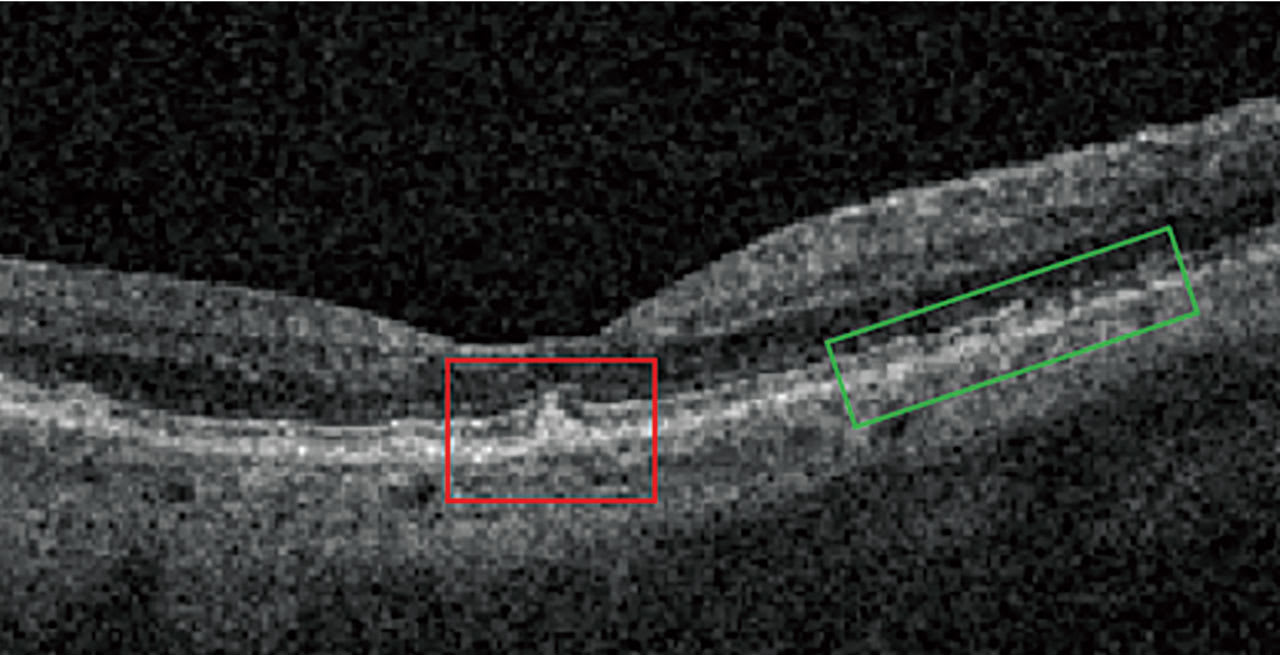

On OCT, drusen appear as RPE elevations. Calcified drusen have a hyporeflective core surrounded by a hyperreflective area on OCT (Figure 3). Patients who have heterogeneous internal reflectivity within drusen (HIRD) have a 6-fold risk of progressing to advanced AMD within a year.4

Reticular Pseudodrusen and Subretinal Drusenoid Deposits Reticular pseudodrusen (RPD), also called subretinal drusenoid deposits (SDD), are anterior to the RPE layer and have a reticular pattern of yellow-white lesions on CFP. RPD are associated with multifocal GA lesion development.1 On OCT (Figure 3), RPD are hyperreflective above the RPE (drusen are below the RPE). Patients who have RPD have a 2-fold increased risk of progressing to advanced AMD.5